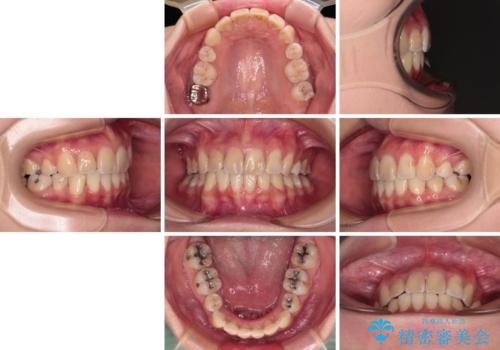

デコボコと深い咬み合わせ ワイヤー装置での抜歯矯正

- 内側に倒れ込んだ歯や下の前歯が隠れてしまうほどの咬み合わせを改善したいとのことで来院された患者様です。

下顎の叢生を解消するために抜歯が必要であり、奥歯の咬み合わせや口元の印象から、上顎も同様に抜歯と判断し、上下左右の第1小臼歯4本抜歯してワイヤー装置にて矯正治療を行うこととしました。

咬み合わせが深く、そのままでは上顎の抜歯スペースが閉じきらない可能性があったため、治療初期から深い咬み合わせを改善させるように試みました。

実際にはなかなか改善されず、当初予定よりも治療期間がやや長期化してしまいました。